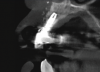

In this case, a dental implant that had been placed 10 years prior was functional, stable, and esthetically acceptable to the patient. However, a significant fistula was present on the facial-apical aspect of the ridge in the maxillary lateral incisor area. This area was painfully sensitive to touch and demonstrated purulence when squeezed. To evaluate the lesion, first, a conventional digital radiograph was acquired, which revealed an apical radiolucency at the apex of the implant (Figure 1). Further analysis using cone-beam computed tomography (CBCT) demonstrated a fistula from that site to the oral environment (Figure 2). Treatment options were discussed, including removal of the implant, followed by grafting, a healing period, and replacement of the implant and implant-retained crown. If this option was selected, a transitional appliance would need to be created. Another option was to attempt to salvage the implant and implant crown by treating the infection and grafting the site to create a new boney wall and eliminate the fistula. Ultimately, the patient accepted this option to attempt to salvage the fixture and crown.

Peri-implantitis was not the culprit behind the creation of this infected site; the lesion developed as a result of the position of the implant. Although the implant was initially stable upon placement, it was angled such that its apex had penetrated through the facial plate of bone. Without a sagittal CBCT analysis or a releasing flap performed to evaluate the initial placement, the surgeon could easily miss this. Regardless, the circumstances warranted evaluation of the apical aspect of the implant to attempt to salvage it.

(2.) Preoperative CBCT analysis demonstrating a fistula from the site of the radiolucency to the oral environment.

Figure 2